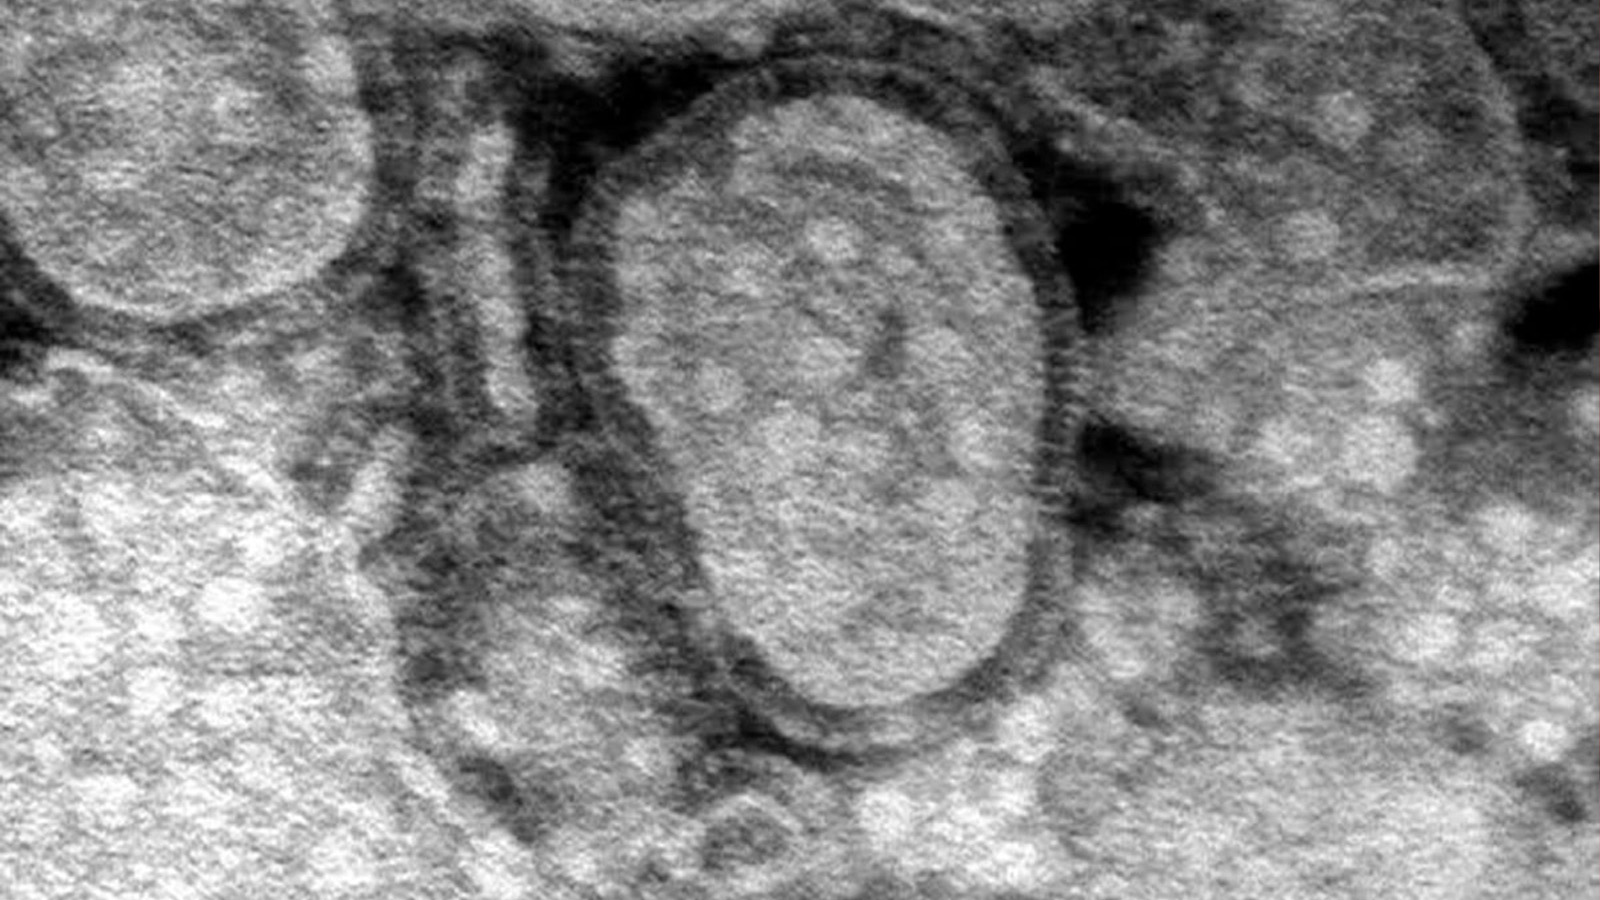

Cinco años después de la pandemia de Covid-19, China se enfrenta a un nuevo brote de metapneumovirus humano (HMPV), una enfermedad respiratoria que está comenzando a llenar hospitales en diversas regiones del país. Según informes recientes, el HMPV, que presenta síntomas similares a los de la gripe y el Covid-19, ha generado un aumento de consultas médicas y hospitalizaciones, especialmente entre los más jóvenes. Además, otros virus, como la influenza A y Mycoplasma pneumoniae, están circulando, lo que ha generado preocupación en las autoridades sanitarias.

Los videos compartidos en redes sociales muestran hospitales desbordados, lo que ha generado especulaciones sobre un posible estado de emergencia. Algunos usuarios informan que los crematorios también están sobrepasados por la alta mortalidad, particularmente en casos graves de neumonía progresiva, descritos como “pulmón blanco”. Aunque no se ha confirmado la declaración oficial de emergencia, las autoridades chinas están implementando un sistema de vigilancia para la neumonía de origen desconocido, con el objetivo de manejar nuevos patógenos y fortalecer la respuesta ante futuras epidemias.

El HMPV afecta principalmente a niños menores de 14 años y es especialmente prevalente en la región de Uttar Pradesh. A pesar del aumento de casos, los expertos aseguran que el número total de infecciones respiratorias este año será menor que en 2024. Sin embargo, alertan sobre el uso indiscriminado de medicamentos antivirales, ya que no existe una vacuna para tratar el HMPV.

El brote ha puesto de relieve los desafíos de salud pública que enfrenta China, mientras se preparan para enfrentar más enfermedades respiratorias durante la temporada de invierno y primavera.